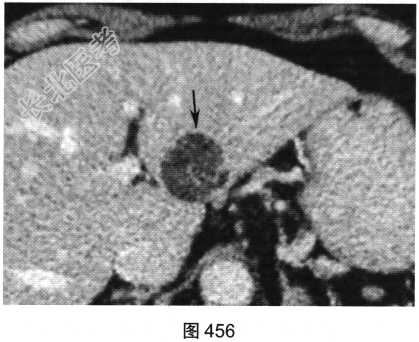

- [材料题] 患者女性,63岁,长久上腹痛并恶心、呕吐、寒战入院。超声提示肝脏有一高回声、边界清的肿块。患者进一步行肝脏CT检查,如图454~图456所示。

- 多项选择题1.对上述CT图像表述不正确的是( )

A、病灶位于肝S2/3,边界清

B、平扫病灶为低密度

C、门静脉期病灶无强化

D、动脉期病灶不均匀强化

E、动脉期病灶无强化

F、门静脉期病灶内线状轻度强化

- 多项选择题2.该病例最合适的诊断是( )

A、脂肪肉瘤

B、血管平滑肌脂肪瘤

C、脂肪瘤

D、肝细胞癌

E、淋巴瘤

F、肝局灶性结节增生